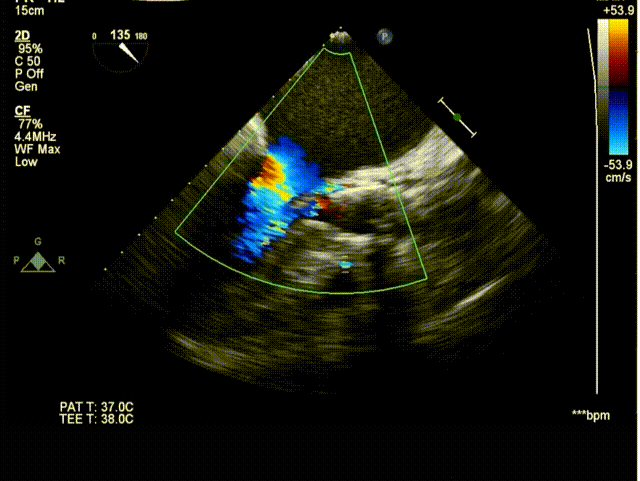

男,78岁,因“发作性胸痛10余年,加重2月”入院。超声检查主动脉瓣Vmax = 4.1m/s ,PGmain=41 mmHg,EF值60%,诊断为重度主动脉瓣狭窄。

植入后超声评估: